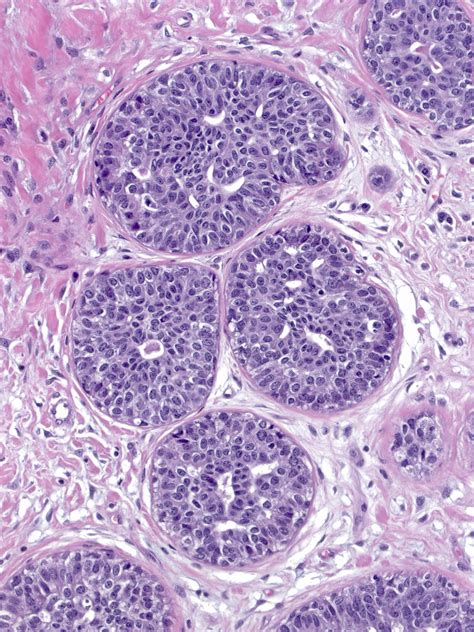

To understand Atypical Ductal Hyperplasia, it helps to look at how breast tissue changes. In a healthy breast, cells line the ducts (the tubes that carry milk). Sometimes, these cells begin to grow in an uncontrolled or disorganized manner. This process is called hyperplasia.

When those cells not only multiply but also begin to look and behave differently than normal cells—yet are not considered cancer—it is classified as “atypical.” Therefore, ADH represents a state of overgrowth where the cells lining the breast ducts have acquired some features of cancer but remain confined within the ductal structure. It is essentially a marker that indicates your breast cells are prone to genetic changes that could lead to breast cancer in the future.